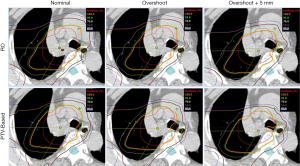

For better illustration of sensitivity to range and setup uncertainties, we compared the dose distributions in transverse plane. Figure 1 is the comparison result of one lung case. Left panels are dose distributions in nominal position; the middle panels are corresponding data with +3.5% over-range, and the right panels are for +3.5% over-range plus 5mm shift in all directions. The underdose regions appeared in the scenarios of overshoot and displacement by using PTV-based optimization, whereas the target remained better dose coverage in the RO plan. This result demonstrates the insensitivity of the RO plan to proton uncertainties compared with the PTV-based optimized plan.

Figure 3 and Figure 4 show the transverse dose distribution and DVH for one head-and-neck case. The dose distribution in the RO plan was insensitive to range and setup uncertainties compared to PTV-based plan. The DVH bands of target was narrower for the RO than PTV-based plan. The sigma value was also smaller which indicates the plan has less response to proton uncertainties. Both the head-and-neck and lung cases showed similar results.